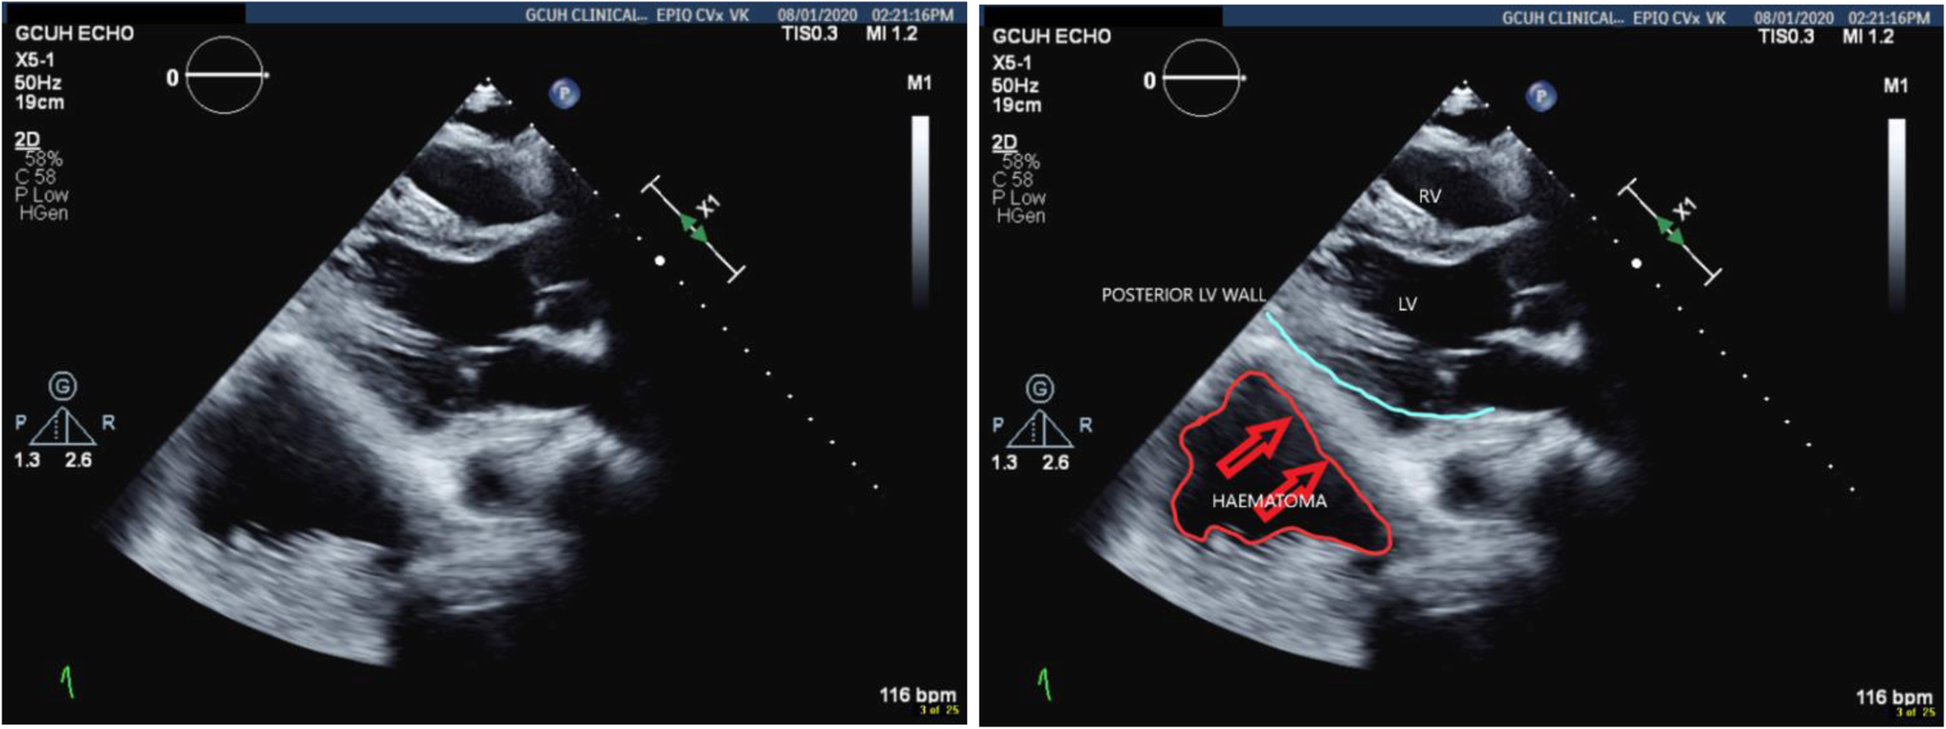

TTE confirmed retrocardiac compression as a result of the expanding retroperitoneal haematoma (Figs. 6 and 7).

Fig. 6

Parasternal long axis view showing the haematoma compressing the posterior wall of the LV

Bild vergrößern

Fig. 7

Short axis view showing the haematoma compressing both posterior and inferior walls of the LV